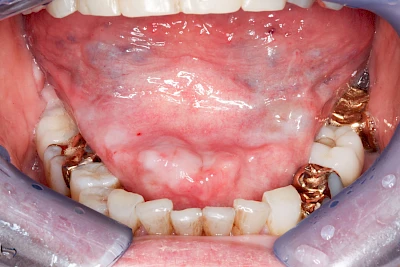

Milchiges bzw. gelbliches Sekret im Bereich der Speichelausführungsgänge entweder an den Wangeninnenseiten auf Höhe der ersten großen Backenzähne im Oberkiefer oder unter der Zunge können auf Entzündungen der großen Spreicheldrüsen hinweisen. Ebenso Schwellungen bzw. Auftreibungen, Rötungen oder spürbare Wärme einseitig unterhalb eines Ohrs und im Bereich des Kieferwinkels.

Einzündungen der kleinen Speicheldrüsen im Gaumen fallen dagegen durch kleine punktförmige Rötungen auf. Wenn ausreichende Flüssigkeitszufuhr und ggf. sanftes Massieren der Speicheldrüsen und der Ausführungsgänge (z. B. Parotitisprophylaxe) keine Verbesserung erzielen lassen oder wenn zusätzliche Symptome wie z. B. Fieber auftreten, sollte ein Arzt oder Zahnarzt hinzugezogen werden.